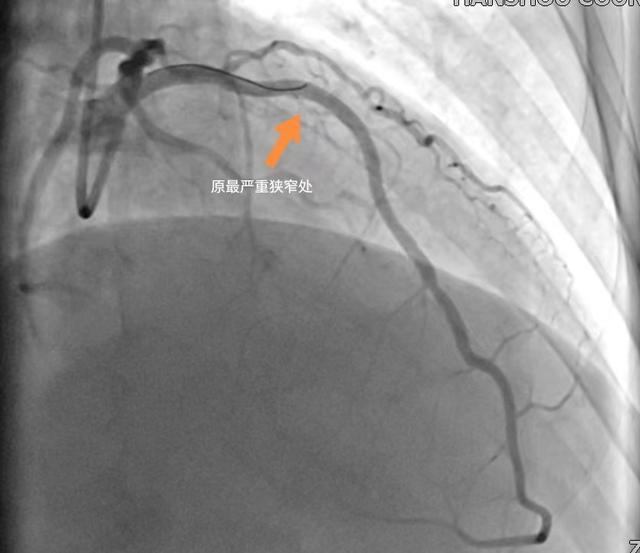

术中IVUS超声提示前降支近段斑块负荷84%,最狭窄处管腔面积1.61mm2,在IVUS指导下完美扩张了病变,成功植入支架后复查,IVUS提示支架膨胀、贴壁良好,无夹层,原最狭窄处管腔有效面积5.75mm2。

(冠脉介入治疗后)